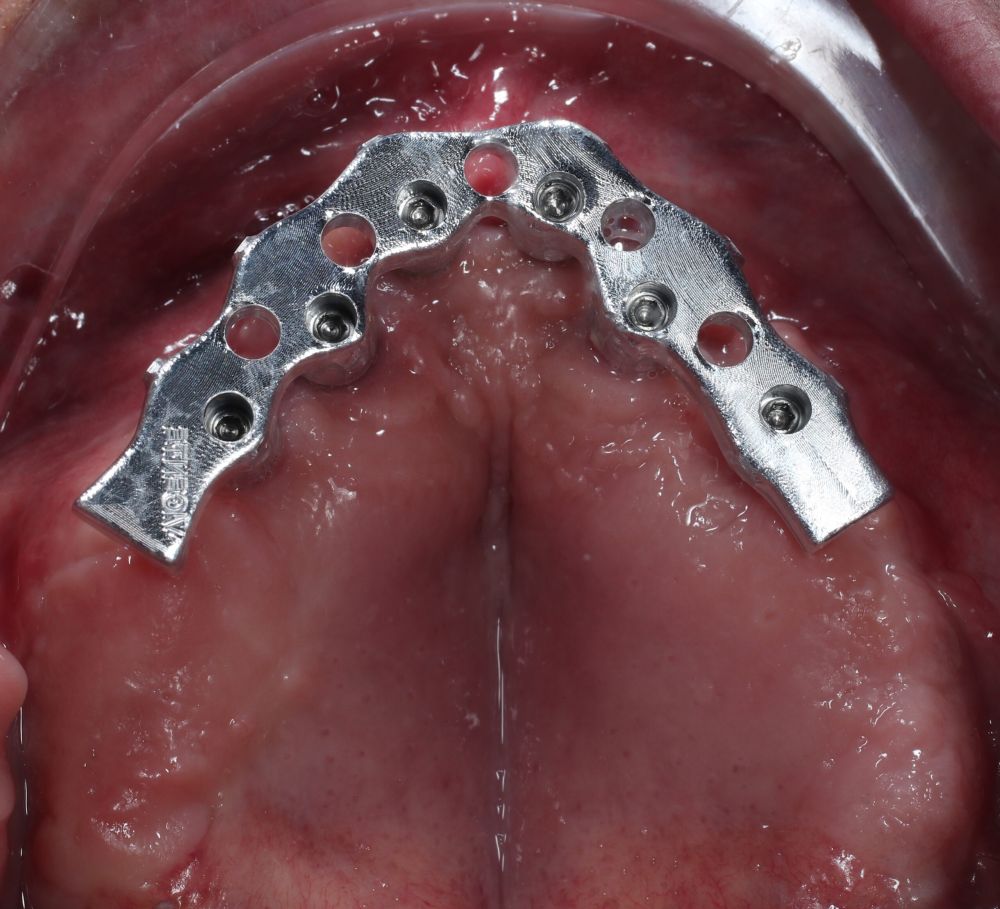

Two months later, with the soft tissues healed around the connections (Figure 16), a new intraoral scanning was made of the implants and the provisional prosthesis for future restoration. A FRI type passivity test (rigid impression splint) was manufactured with an aluminium structure to assess the correct fit on the implants (Figure 17). For implant-supported rehabilitation, a sintered structure was made in chrome-cobalt with machined bases covered with acrylic resin teeth from Bredent® (Figures 18-21).